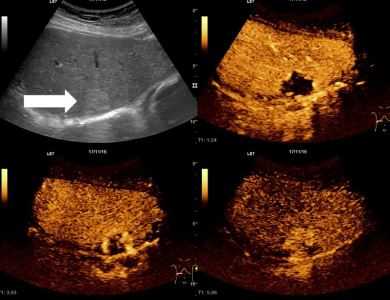

Гемангиома печени на УЗИ

Гемангиома — это сосудистое образование внутри печени, состоящее из сплетения кровеносных сосудов. Оно носит доброкачественный характер, но имеют склонность к увеличению в размерах. Кавернозная опухоль достигает в диаметре до 20 см, и при отсутствии лечения превращается в атипичную гемангиому, покрытую ороговевшей тканью.

Опухоль легко диагностируется на УЗИ, она имеет чёткие бугристые контуры и гиперэхогенность. Повышенный кровоток подтверждается при помощи допплеровского сканирования. Однако УЗИ только подтверждает сам факт наличия опухоли, но более достоверные сведения даёт МРТ.